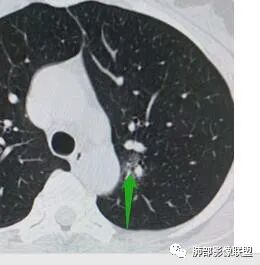

一.尖后段高密度大结节:

1.左肺上叶尖后段较大类圆形实性密度结节影,密度均匀,中等程度强化。

2.实性密度区边缘相当清楚,表面欠光整,偶见毛刺、棘突和旁出血管结构,未见典型的深分叶及邻近胸膜凹陷。

3.可疑支气管进入受阻。可惜缺乏连贯图像或冠矢状位以资判断。

4.病灶与胸膜之间有连线,邻近段支气管及肺血管整体后移,提示病灶还是有一定收缩性。

如上,单就这实性结节,硬化性肺细胞瘤(PSP)和腺癌似乎都能够解释,形态太规整了一些。

5.病灶周围见边界清楚的磨玻璃影,有点醒目,有点意外!

这是无论如何不能忽视的征象!

这点强烈提示,要么整个病灶恶性(腺癌),要么良性病灶旁滋生恶性病灶。

两年前左上肺的病灶什么位置,什么模样,是否相关?我们不得而知。